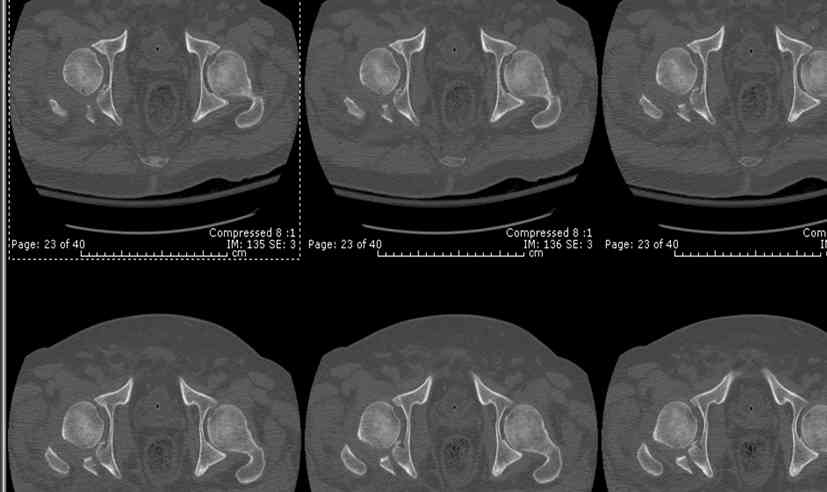

45 yo male in MVA, only other injury=small subarrachnoid bleed (neurologically fine, GCS never <14), with this transverse & associated posterior wall fx-dislocation 7/7

In skeletal traction thru distal femoral pin 40 lbs with decent reduction - except for the free fragments in the hip joint. ORIF planned for post-injury day 11.

Biggest problem appears to be impaction & comminution of the posterior wall fx site - you've left out some CT cuts. This is not just fragments in joint. It may leave a deficient area, &/or block satisfactory posterior wall reduction.